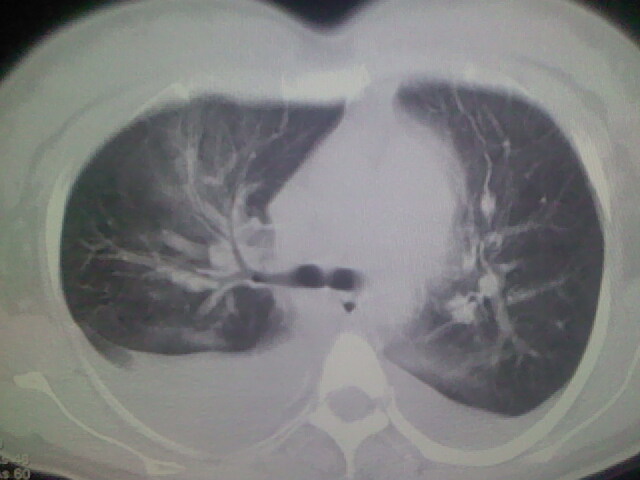

女,24,剖腹产后,突觉胸痛,干咳,不能平卧

做个增强的 ct吧 pte(肺血栓栓塞)不能除外啊 在结合心电图 看看v1-v4导连的t波及st段改变。

患者允许的情况下建议进行心脏超声检查

肝脾大,双侧胸腔积液,双肺水肿,肺动脉[包括远端小动脉],左右心房,左心室增宽,右心室主动脉无明显改变,符合左心功能不全征;;建议除外二尖瓣关闭不全,扩张性心肌病

急性心衰可能,肺梗塞??我没看到病变的具体位置,楼上的给讲讲啊

考虑肺梗塞 双侧胸腔积液 心影增大 建议进一步检查吧